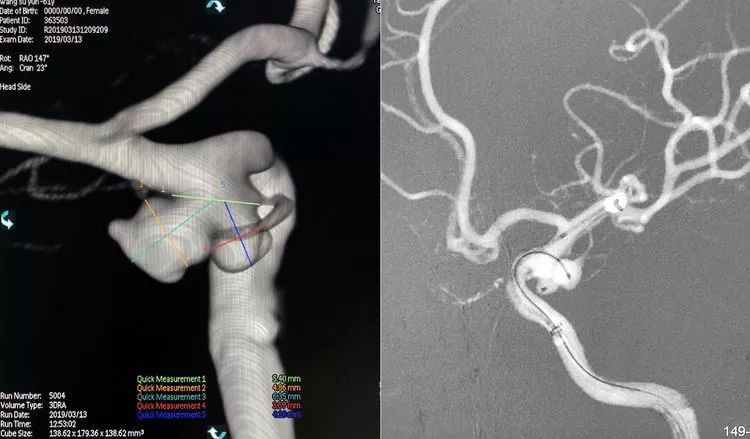

mm3,一级螺旋最粗(0.0145 in.)的弹簧圈其厘米体积为1.07 mm3。以MicroVention弹簧圈为例,一级螺旋最细(0.0100 in.)的弹簧圈其厘米体积为0.51 mm3,一级螺旋最粗(0.0150 in.)的弹簧圈其厘米体积为1.14 mm3。粗略来说,各种弹簧圈的厘米体积平均为0.8 mm3。后面有一个动脉瘤的演示病例,先提上来分析,动脉瘤大小7.27 mm×6.04 mm×6.46 mm,则动脉瘤致密栓塞所需弹簧圈总长度=[7.27×6.04×6.46÷2]×30%÷0.8=53 cm。一般首枚弹簧圈的长度钦定为总长度的1/3到1/2(18~27 cm),那么这个区间内最常备的长度规格就是20 cm。根据动脉瘤短径6.04 mm,首枚弹簧圈的直径选6 mm,所以首枚弹簧圈的规格就出来了:6~20。